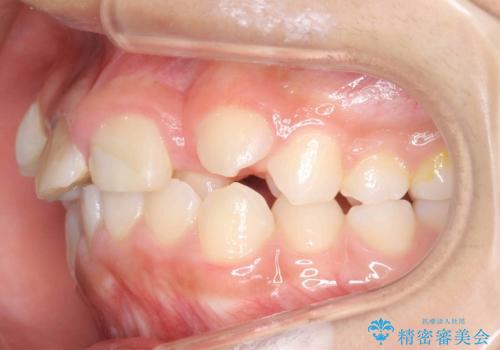

- 前歯のガタガタを主訴に来院。

上の前歯は、小さいころにぶつけて折ったとのことで、神経が死んでおり、根の治療が必要な状態でした。

左上の前歯は神経が死んでおり治療が必要な状態でした。また、右上の前歯も根の先に感染がありましたので治療を行いました。

また、プラスチックでつぎはぎになっていたため、虫歯を取りしっかりとしたクラウン(被せもの)としました。